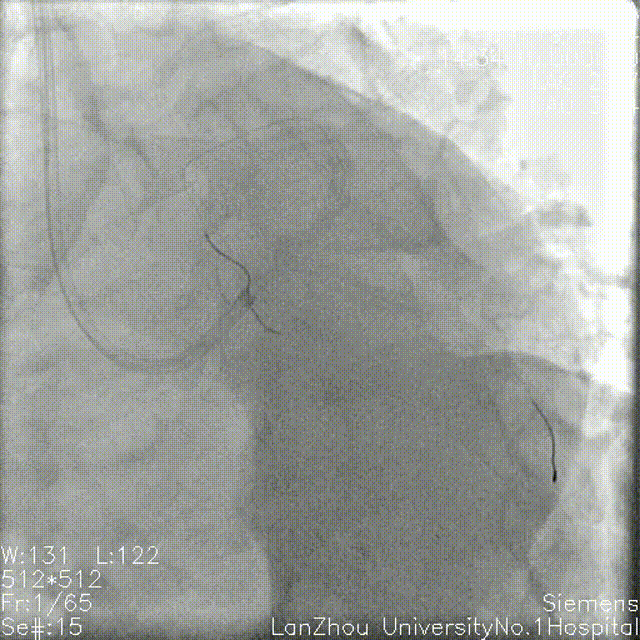

蜘蛛位造影:

左主干开口、体部未见明显狭窄;

第一对角支开口重度狭窄;

回旋支次全闭,开口、近端、中段重度狭窄,可见环形钙化。

右冠造影:

全程斑块伴有钙化;

第二弯可见支架影,支架未见明显再狭窄。